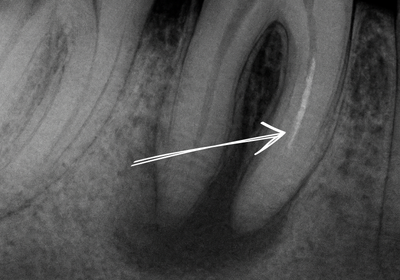

Zajímavost o MB2 kanálku

Druhý mesiobukální kanálek (MB2) u horních molárů je nejčastěji přehlédnutým kanálkem v endodoncii. Bez mikroskopické techniky jej najde pouze 55 % lékařů, zatímco s mikroskopem až 93 %!

- Detekce MB2 se zvyšuje ze 55 % na 93 % (De Moor et al., 2010)

MB2 je druhý mesiobukální kanálek u horních molárů. Bývá úzký, zakřivený a anatomicky blízko prvního mesiobukálního kanálku, takže při vyšetření bez zvětšení snadno unikne pozornosti. Bez mikroskopu jej najde jen 55 % lékařů, s mikroskopem až 93 %. Přehlédnutý MB2 je hlavní příčinou selhání endodontické léčby u horních molárů.